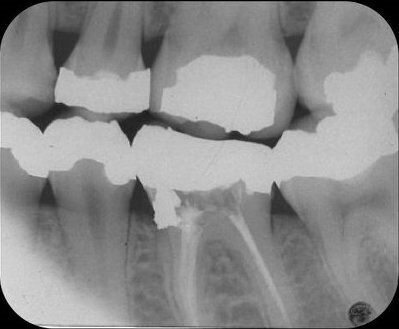

Tijdens het zoeken van de kanaalingangen met een ronde boor veroorzaakte ik een perforatie naar mesiaal (afb. 2), die zichtbaar werd nadat ik een lengtefoto had genomen, waarbij een vijl door de mesiale begrenzing van de mesiale radix stak.

Afb. 2: Lengtefoto van de mesiale kanalen, waarbij een handvijl in de perforatie steekt